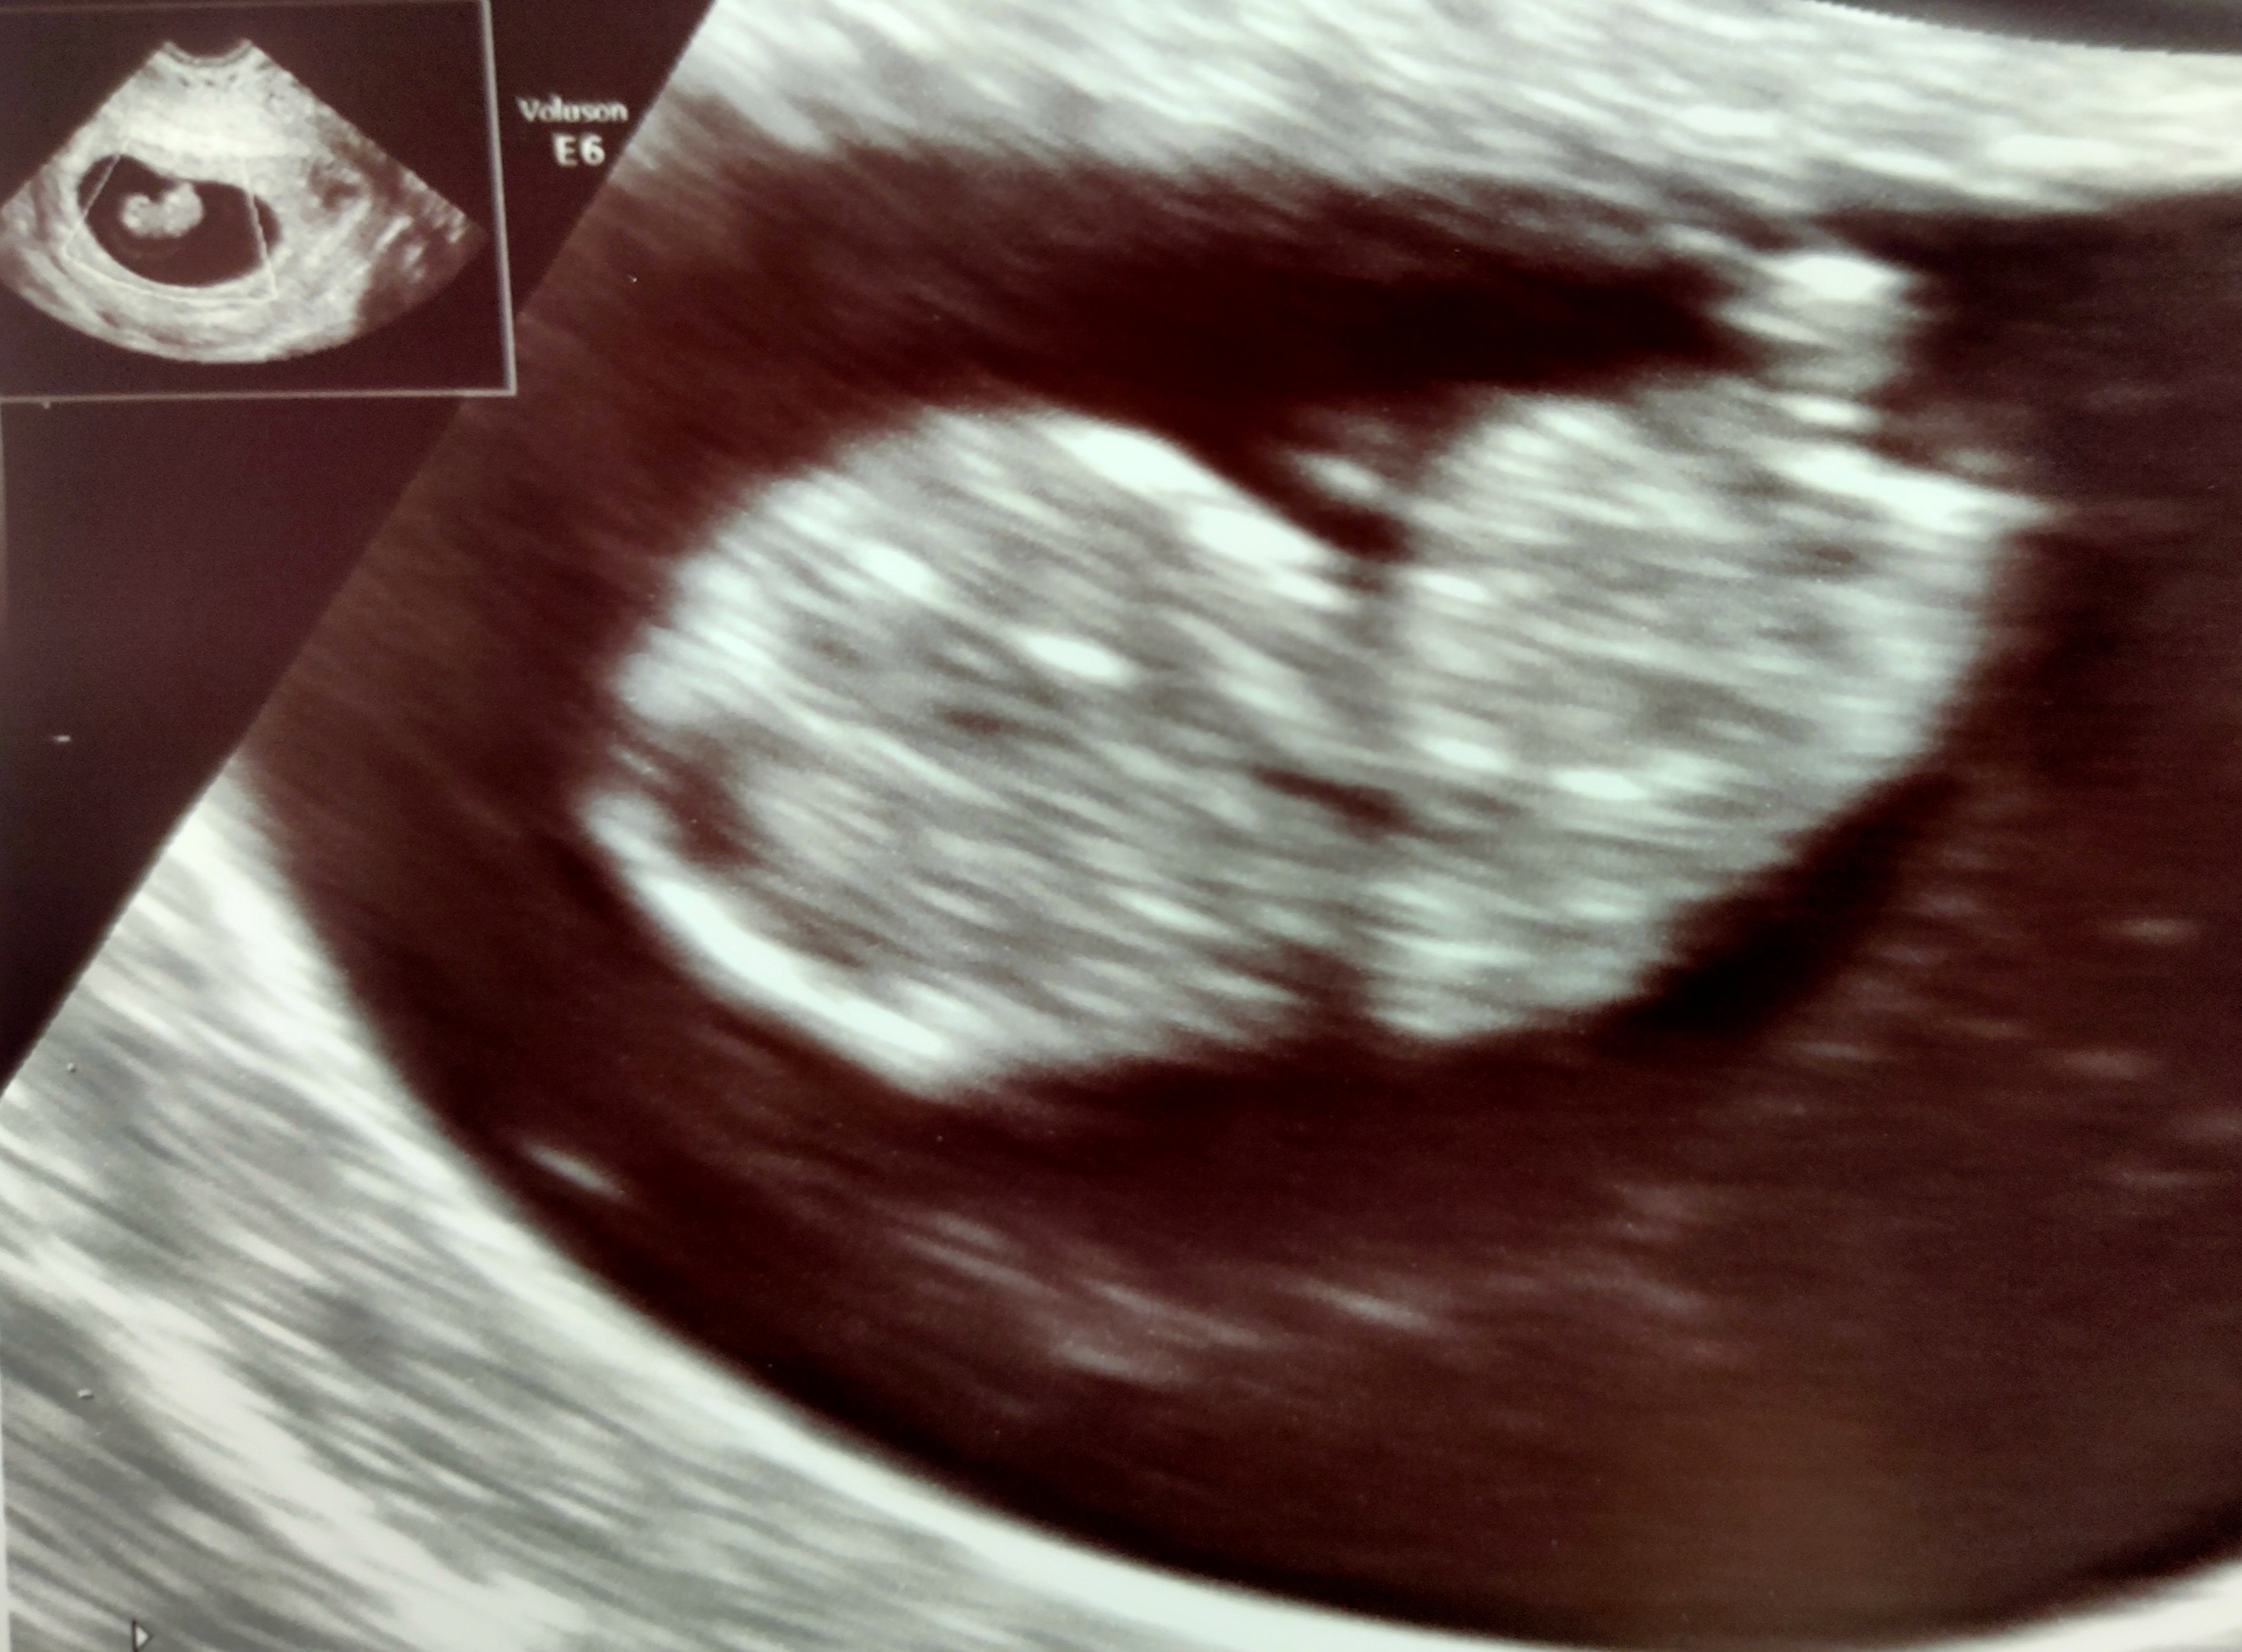

Jestem po wizycie ;) widać główkę, nóżki, rączki i bijące serduszko (ale nie słuchaliśmy). Ma 2.14cm. z om 7+6, z usg 8+5. Termin na 6 maja ❤️ Mogę zapisywać się na prenatalne bo wszystko dobrze.

Załączniki

• IMG_20200929_161831.jpg

IMG_20200929_161831.jpg

999,6 KB · Wyświetleń: 134